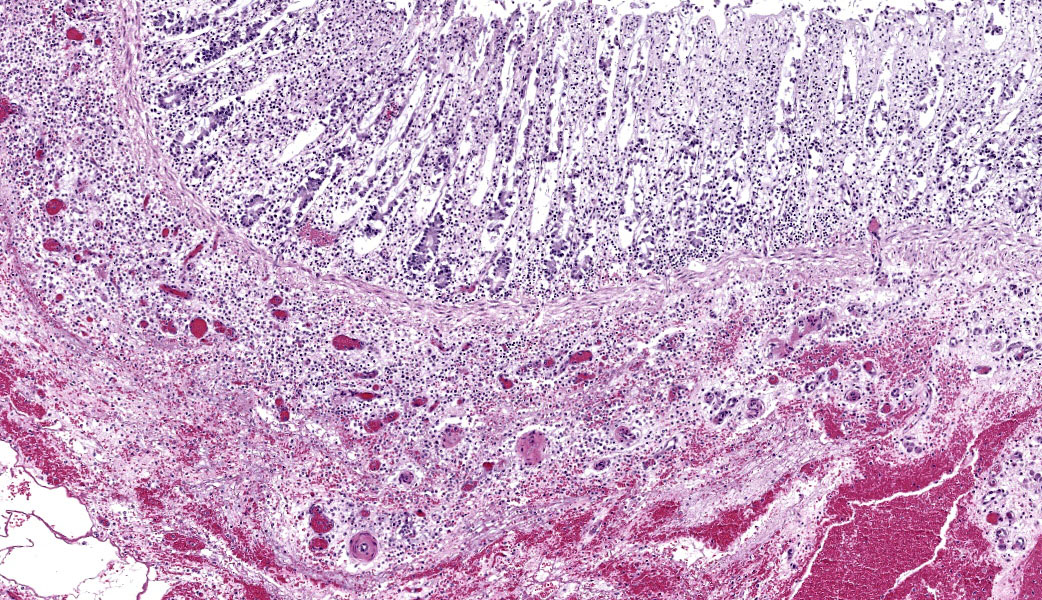

Colon: There is severe, diffuse necrosis of the mucosa where the superficial epithelium and, less prominently, the crypt epithelium is lost and/or show hypereosinophilia, pyknosis, karyorrhexis and karyolysis. The lamina propria is diffusely eosinophilic and infiltrated by a large number of viable and degenerated neutrophils and fewer neutrophils, plasma cells and macrophages; this cellular infiltration extends to the submucosa. Multifocally, the mucosa is covered by a thick pseudo membrane composed of fibrin, cell debris, red blood cells, neutrophils and myriad mixed bacteria. Several blood vessels of the lamina propria show thrombosis. In areas where the superficial epithelium is still present, erosions are seen through which large number of neutrophils are seen exiting the lamina propria into the lumen (volcano lesions). The submucosa is severely dilated and edematous; there is vascular congestion and the lymphatic vessels are dilated. The serosa shows reactive mesothelial cells.

Colitis, fibrinonecrotizing, diffuse, with thrombosis, volcano lesions, submucosal edema and mixed bacteria

cocktail of anti-toxin A and anti-toxin B antibodies, the positive result means that in the intestinal content there was one of the two toxins.6 Isolation of C. difficile is suggestive of this microorganism involvement in the colitis, but not confirmatory as a number of clinically healthy horses can harbor C. difficile in the intestine.4,5,6,7 Likewise, both gross and microscopic lesions are suggestive of, but not confirmatory, C. difficile infection. In particular, the volcano lesions are considered highly suggestive for C. difficile infection; this finding should, however, be interpreted with care, as other pathogens can also cause this lesion.3,4,7

Colon: Colitis, fibrinonecrotic, subacute, diffuse, marked, thrombosis, edema, and volcano lesions.

Clostridioides difficile (renamed in 2016 from Clostridium difficile) affects many species of all ages.1,3 The primary clinical sign is profuse diarrhea. Histologically, "volcano lesions", as seen in this case, are a hallmark of C. difficile in the acute phase of infection.3,4 Although other organisms (including Salmonella) can cause these lesions, they are considered classic for C. difficile. These lesions are characterized by micro-ulcerations of the mucosa with necrotic debris and neutrophils being "spat out" into the lumen, giving it the appearance of lava spewing from an erupting volcano. Following acute infection, volcano lesions become difficult to see histologically due to the progression to a full-blown necrotizing colitis, the lesions of which are non-specific and can be caused by a number of enteric pathogens (i.e. Salmonella spp, Brachyspira spp, etc.). As mentioned by the contributor, culture is a more suggestive method for confirming a diagnosis of C. difficile, but the results must be interpreted with caution as, according to Dr. Uzal, 3% of clinically normal horses will grow C. difficile on culture of enteric content.4